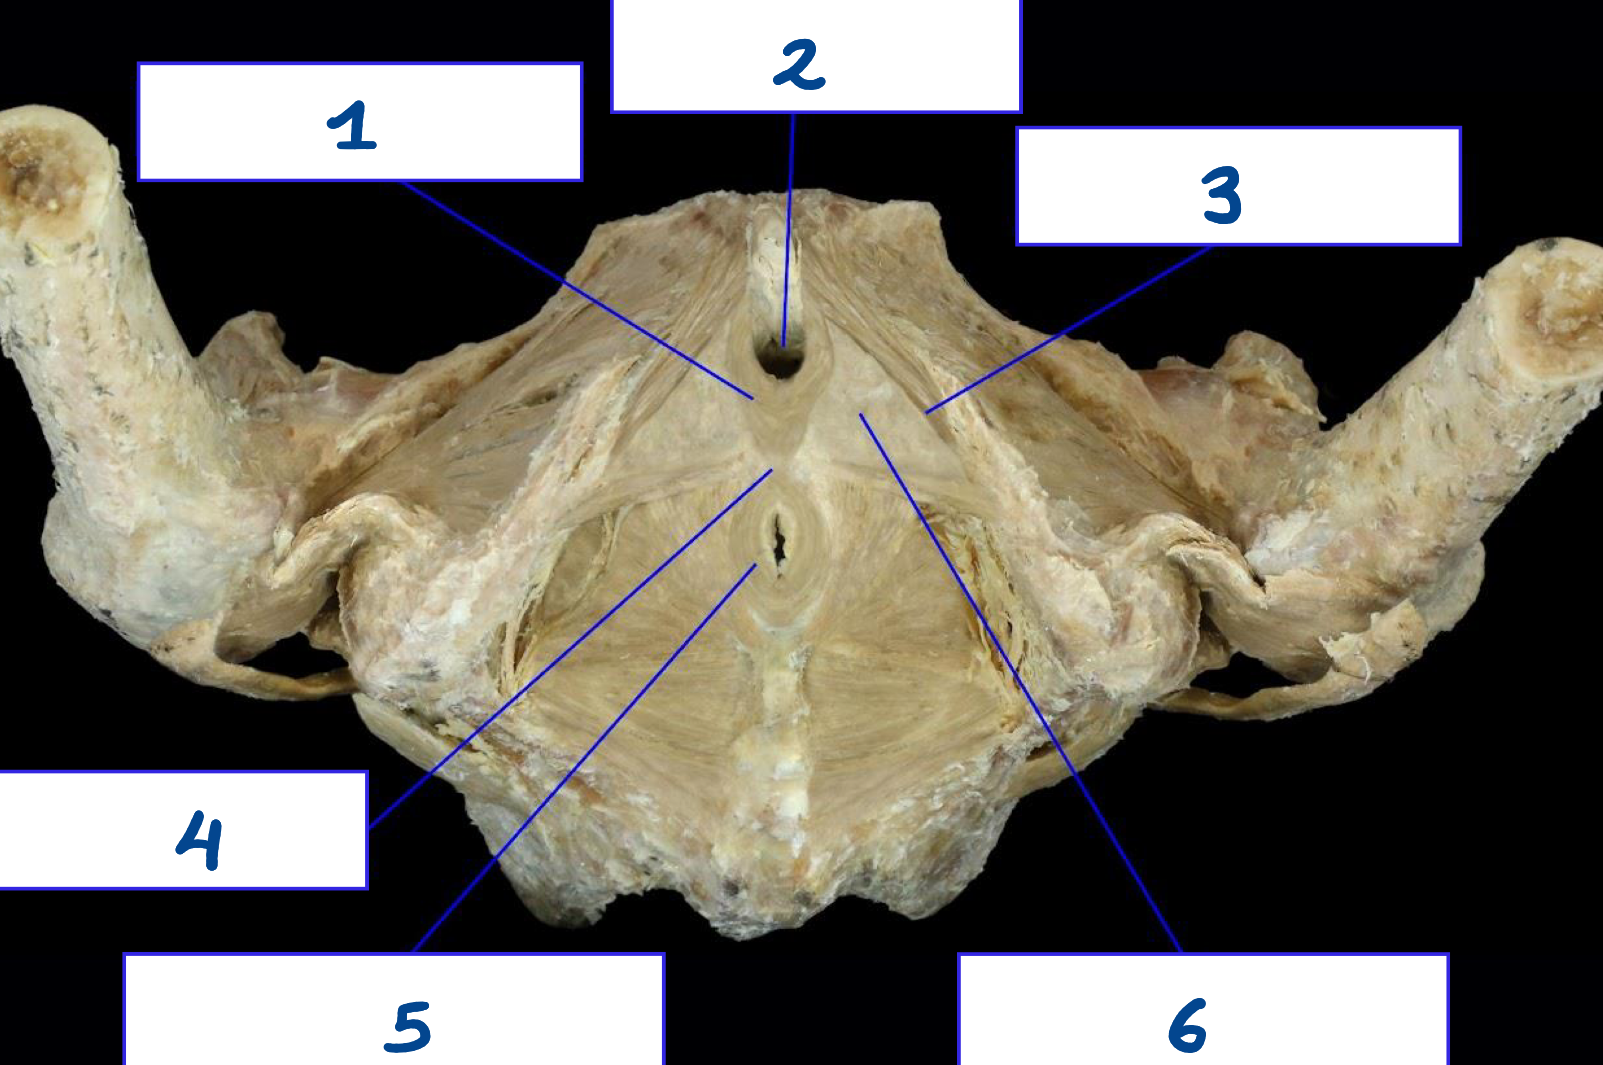

<p>What is structure 1?</p>

What is structure 1?

Greater sciatic foramen

<p>What is structure 2?</p>

What is structure 2?

Lesser sciatic foramen

<p>What is structure 3?</p>

What is structure 3?

Sacrospinous ligament

<p>What is structure 4?</p>

What is structure 4?

Sacrotuberous ligament

<p>What is structure 5?</p>

What is structure 5?

Obturator membrane

<p>What is structure 6?</p>

What is structure 6?

Obturator canal